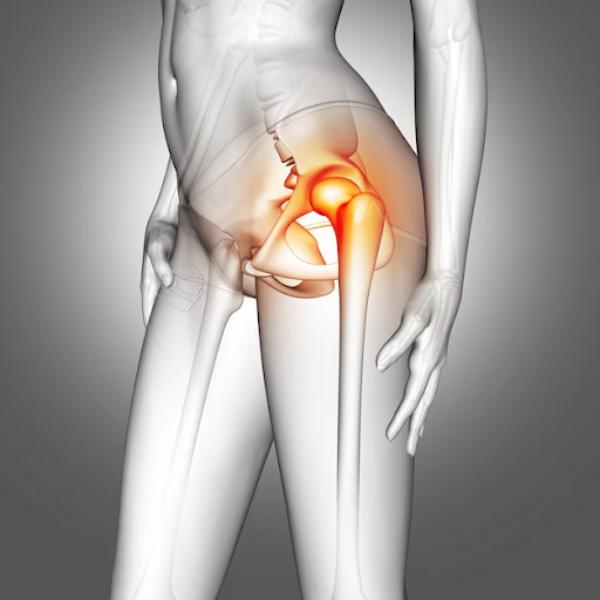

What We Cure

Shoulder Arthroplasty

Shoulder arthroplasty is a surgical procedure used to replace damaged or arthritic parts of the shoulder joint with artificial components. It is typically recommended for patients with severe osteoarthritis, complex fractures, or rotator cuff-related joint degeneration that limits mobility and causes chronic pain. At Rapha Sports and Regenerative Orthopaedics, our surgeons offer advanced shoulder replacement options tailored to each patient’s condition, lifestyle, and functional goals. Types of Shoulder Arthroplasty: Total Shoulder Replacement (Anatomic): Replaces both the ball (humeral head) and socket (glenoid) with prosthetic components. Best suited for patients with intact rotator cuff muscles and primary osteoarthritis. Reverse Shoulder Replacement: Reverses the normal anatomy of the shoulder by placing the ball component on the shoulder blade and the socket on the upper arm. Ideal for patients with rotator cuff tears, cuff tear arthropathy, or complex fractures. Hemiarthroplasty: Replaces only the ball portion of the joint. Often used in certain fractures or where the socket remains healthy. Partial/Stemless Shoulder Replacement: A bone-preserving option for select patients with less extensive damage, offering quicker recovery and less invasive techniques. Our multidisciplinary team ensures seamless care—from pre-operative planning to post-operative physiotherapy—focused on restoring function, reducing pain, and supporting long-term joint health.